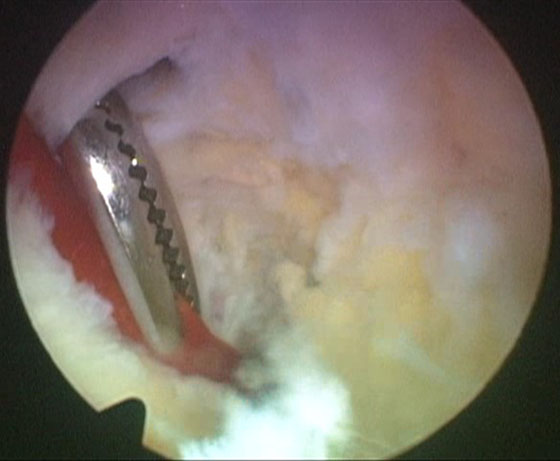

Se procede luego a realizar el portal posterointerno. Dado que no se reseca el remanente HPM, el espacio para acceder a la cápsula posterointerna se encuentra reducido, para ampliarlo realizamos una mínima “notchplastia” en la parte posterior del cóndilo interno (Fig. 4). Con la visión desde el portal anterointerno colocamos un switcher, de los utilizados en cirugía de hombro, desde el portal anterolateral ubicándolo entre el remanente ligamentario y el cóndilo interno (Fig. 5). Luego se pasa la cánula de irrigación guiada por el switcher y se accede con la óptica a la cápsula posterointerna, bajo visión directa colocamos una aguja espinal para localizar el portal, completando con bisturí para luego colocar la cánula de trabajo (Fig. 6). En este punto se vuelve a pasar el artroscopio al portal anterointerno, se introduce el shaver por la cánula del portal posterointerno, y se realiza la limpieza de la capsula posterior, siempre con la hoja de corte hacia anterior para evitar la lesión de estructuras vasculonerviosas. Se continúa alternando los portales anterointerno y posterointerno con visión, shaver, pinza basket y raspas de 90º, hasta completar la desinserción de cápsula posterior e identificar el remanente distal del ligamento sin afectar la inserción. En los casos en que la lesión ha sido en la sustancia colocamos la guía tibial distal a la inserción tibial (Fig. 7). Si la lesión ha comprometido la inserción tibial, levantamos la cicatriz que encontremos y colocamos la guía por debajo del remanente (Fig. 8). Para la introducción de la guía sin lesionar los remanentes ni el LCA se coloca la óptica en el portal anteroexterno y se controla el ingreso de la guía por el espacio entre el remanente y el cóndilo interno (Fig. 9). Se pasa el clavo guía, siempre cuidando de llegar en forma motorizada hasta contactar la cortical posterior y se completa el pasaje golpeando con martillo para evitar una salida brusca del mismo. Se pasa la fresa canulada del diámetro adecuado, protegiendo la emergencia de la misma con una cureta. Una vez completado el túnel tibial, se pasa un alambre o cable desde el orificio externo tibial hacia proximal, con visión en portal posterointerno, al ver emerger el alambre o cable por el orificio tibial posterior, se vuelve la óptica al portal anterointerno para controlar el pasaje de un grasper desde anteroexterno a través del intervalo entre HAL y LCA, y dirigirlo hacia posterior (Fig. 10); se vuelve con la óptica al portal posterointerno y se visualiza la recuperación del alambre o cable con el grasper hacia la parte anterior de la rodilla (Fig. 11). Se amplía el portal anteroexterno y se anuda la sutura tractora del injerto al alambre o cable, y traccionando desde el orificio distal del túnel tibial se hace ingresar el injerto en forma retrógrada a la articulación y, luego, al túnel tibial por su orificio posterior. En caso que se utilice el injerto de tendón cuadricipital la parte tendinosa irá al túnel tibial y el bloque óseo al femoral. Una vez ingresado el injerto al túnel tibial, se vuelve la óptica al portal anterointerno, en el portal anteroexterno tendremos la sutura tractora del extremo “femoral del injerto”, es aconsejable en este punto llevar el injerto lo más distal posible para tener mejor visión articular, enhebrar la sutura tractora en una cánula de unos 6 mm de diámetro, para asegurarse que la sutura tractora y la clavija pasasutura pasan por el mismo espacio sin incluir tejido sinovial o grasa retrorrotuliana (Fig. 12). Se procede a pasar la aguja pasasutura por el túnel femoral, saliendo por las partes blandas de la parte medial de la rodilla, se tracciona y se asciende el injerto colocándolo en el túnel femoral. En caso que el injerto tenga bloque óseo puede ser necesario redirigir el mismo para ubicarlo en el túnel femoral, para esto ubicamos la visión en el portal anteroexterno y por el portal anterointerno utilizamos el trocar romo o el palpador para realizar una polea y mejorar la tracción para que ingrese el taco óseo en el túnel femoral (Fig. 13). Luego se realiza la fijación femoral con tornillo de interferencia de titanio o biodegradable. A continuación liberamos el manguito neumático, porque creemos que produce un espasmo en los isquiotibiales que dificulta la reducción de la tibia, dejamos pasar unos minutos que utilizamos para colocar un tornillo maleolar con arandela, distal al orificio externo del túnel tibial para realizar una segunda fijación de la parte tibial. Preferimos hacerlo antes de colocar el tornillo interferencial, porque esto generará una presión hacia posterior de la tibia. Se realiza la reducción tibial en 90° de flexión de la rodilla, se tracciona del injerto y se coloca el tornillo de interferencia tibial, luego la sutura remanente (polyester 5) se anuda en el tornillo maleolar completando la 2da fijación. Por último se constata con una nueva visión articular la posición y tensión del injerto (Fig. 14).

Figura 4